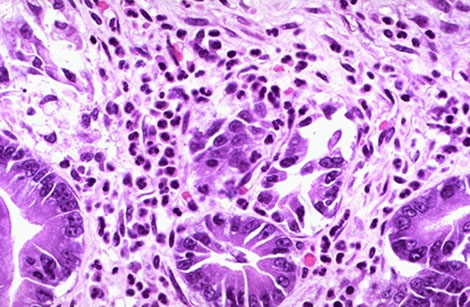

Chronic gastritis in gastric body caused by H pylori

Chronic gastritis

Micro - in type B, see plasma cell and lymphocytic infiltrate in lamina propria c mucosal atrophy and gland loss

- neutros [active gastritis], monos [chronic], lymph aggs / secondary follicles,  erosions, atrophy, foveolar hyperplasia, metaplasia all can be found c H. pylori infx

- may have lymph aggs or primary follicles in normal stomach, but secondary lymph follicles with germinal center should tip you off to ag exposure and thus H pylori